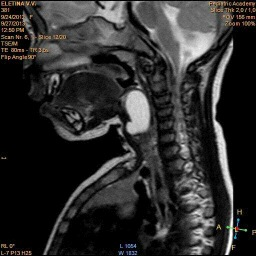

When fibro laryngoscopy revealed a rounded formation of the right vysokopalonadgortnaya fold almost completely overlapping the lumen of the larynx (Figure 1). On a series of MRI tomograms of the soft tissues of the neck from the level of C2 to the level of C5-6 in the projection of the right pear-shaped sinus is determined by a cyst with clear uneven contours, which has an irregular rounded shape. The size of the cyst is 11x16x28mm. Cyst significantly shifts the right scooped-nadgortnaya fold to the left. Its lower edge is traced at the level of the subglottic space (Figure 2-4).

Figure 2:MRI, sagittal projection.